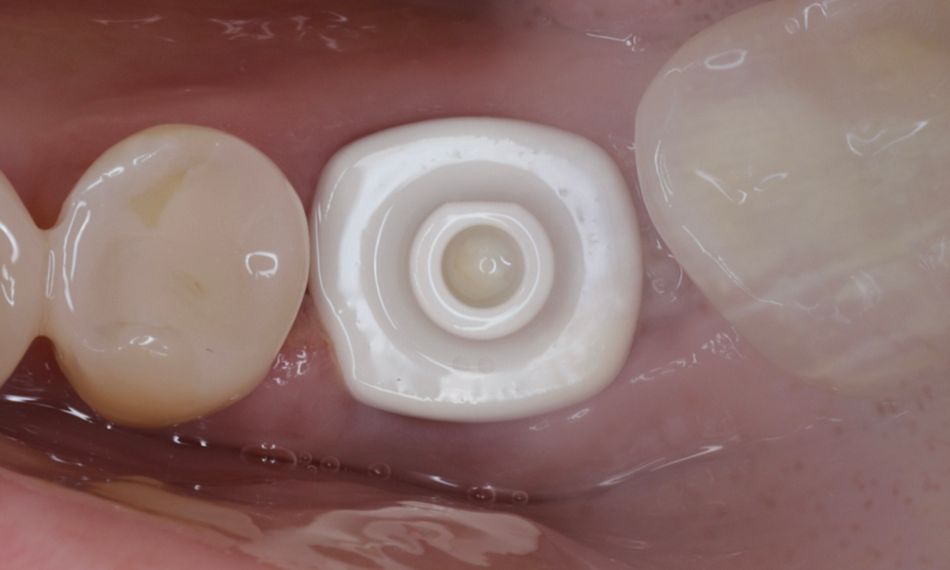

Two months post-surgery, the patient returned for the final prosthetic restoration. Before proceeding with the final restoration, the AHA was thoroughly cleaned and inspected to ensure that no visible defects were present on the scanbody feature (Fig. 7).

Fig. 7

A key advantage of the AHA is that it can be scanned directly without removal, eliminating the need for an extra scan body or additional gingival scans, as its emergence profile is already included in the design software. Scanning was performed intraorally using the Straumann® SIRIOS™ system (Figs. 8-9).

The final restoration was digitally planned, providing full 3D visualization, including critical anatomical details. This workflow enabled the accurate design and fabrication of the definitive restoration on a Straumann® Variobase® abutment, maintaining the same Consistent Emergence Profiles™ and gingival height as the AHA, with the final prosthesis produced as a full-frame zirconia (ZrO) restoration (Figs. 10-13).

Following removal of the AHA, optimal soft-tissue healing was observed. The peri-implant tissues appeared healthy, stable, and well-contoured, demonstrating successful preservation and maturation throughout the healing period (Figs. 14-15).

The definitive restoration was then screwed with a torque of 35 Ncm. Both esthetics and occlusion were carefully evaluated, and the screw access was sealed with PTFE tape and composite (Figs. 16-17).